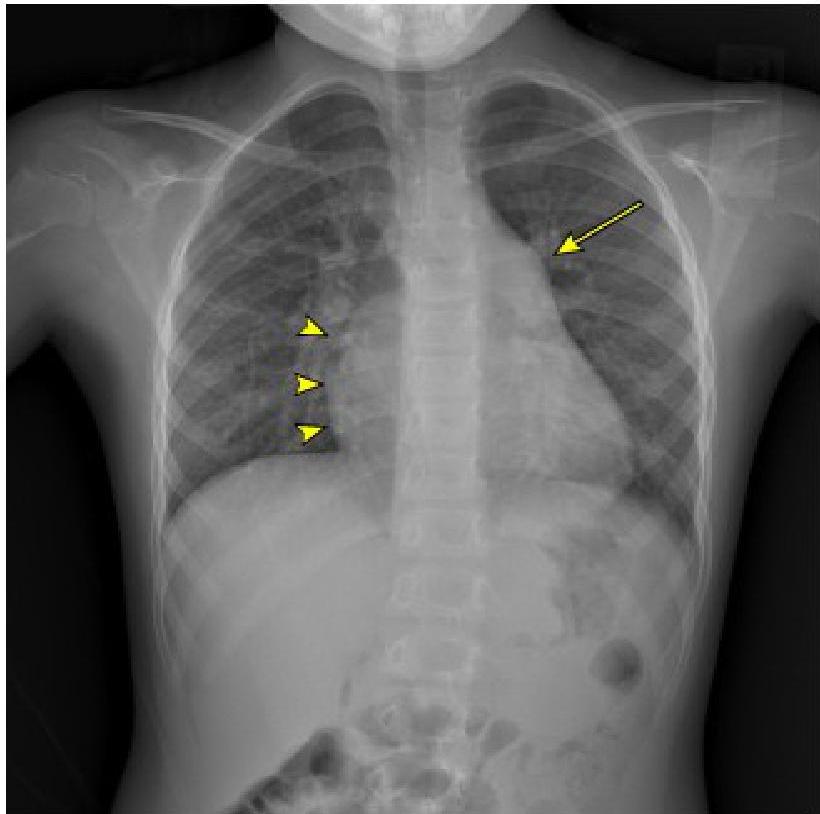

Chest Radiography

- Cardiomegaly: Left-to-right shunting defects, Dilated cardiomyopathy, Myocarditis, and Pericardial effusion.

- Pulmonary congestion/pulmonary edema.

- Pleural effusion.

- Pericardial effusion.

Chest radiograph in a 6-year-old patient with a large secundum atrial septal defect

Demonstrates moderate cardiomegaly with increased convexity of the right side of the heart (arrowheads). There is a large pulmonary outflow tract (arrow) and increased pulmonary vascularity. Findings consistent with large left-to-right shunt.